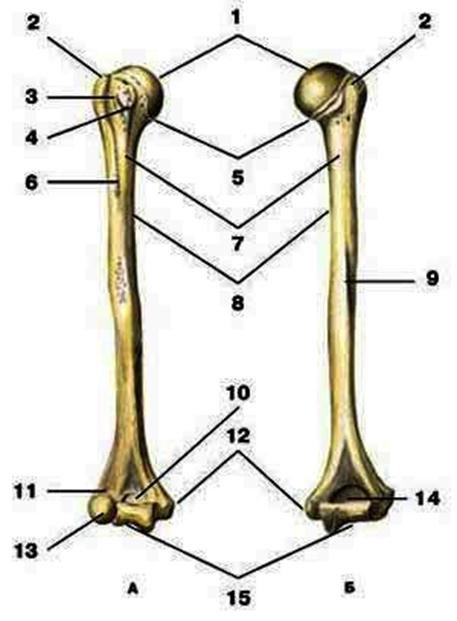

V2:Тема 1.3 Кости верхней конечности и их соединения

S: Цифра 1 обозначает … плечевой кости.

+:сaput

-:t uberculum majus

-:troсhlea

-:capitulum

-:epicondylus lateralis

S: Число 15 обозначает... плечевой кости.

+:trochlea

S: Цифра 5 указывает на...плечевой кости.

+:collum anatomicum

S: Число 10 обозначает... плечевой кости.

+:fossa coronoidea

S: Число 14 указывает на... плечевой кости.

+:fossa olecrani

S: Цифра 9 указывает на... плечевой кости.

+:sulcus nervi radialis

S: Число 12 обозначает... плечевой кости.

+:epicondylus medialis